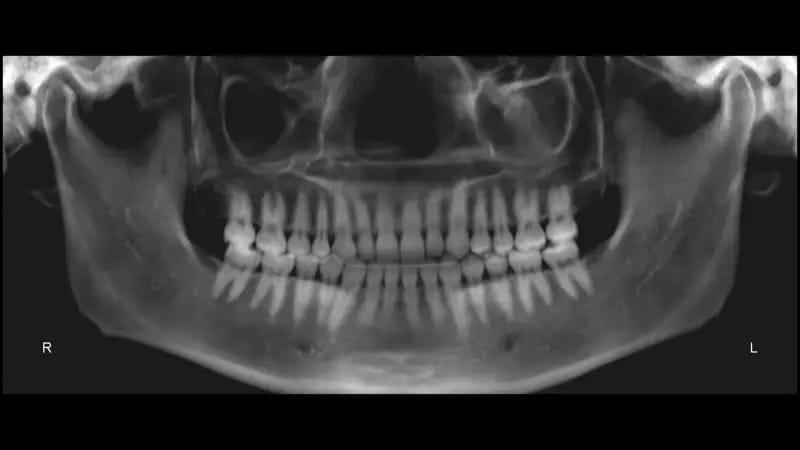

Заключительная панорамная рентгенограмма показала хорошую параллельность корней и подтвердила, что все цели лечения были достигнуты без резорбции корней и вреда для здоровья пародонта (фото 49). Заключительная цефалометрическая рентгенограмма и трассировка подтвердили авторотацию нижней челюсти: лицевая ось составляла 95° до лечения и 97° после лечения, а высота передней части лица составляла 117,5 мм до лечения и 115,9 мм после лечения (фото 50).